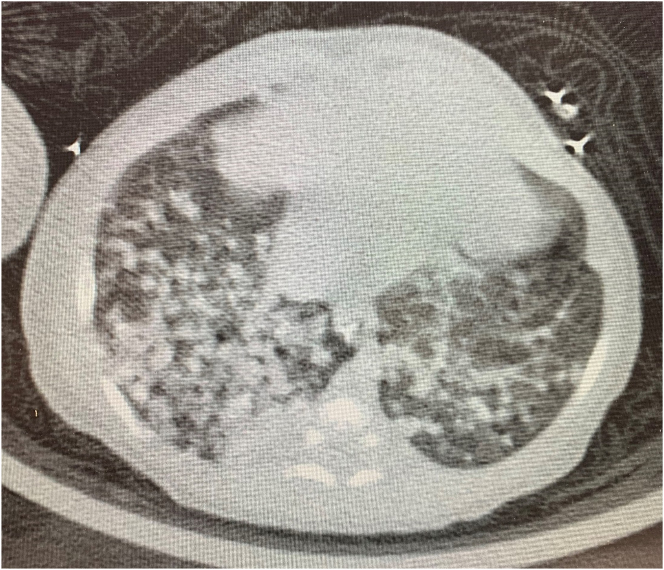

Case presentation: A male infant was born at 33 weeks gestational age to a mother who was hospitalized with respiratory illness and diagnosed with TB after delivery. The diagnosis was based on the presence of granulomas and mycobacteria in the placenta, positive mycobacterium TB PCR in gastric aspirate, and growth of MTB from gastric aspirate and bronchoalveolar lavage cultures. Treatment started initially with isoniazid, rifampin, pyrazinamide, and ethambutol. The patient's clinical course was complicated with ongoing respiratory distress and abdominal distension which raise the possibilities of drug resistance, but sensitivity was confirmed by PCR, or malabsorption of the medications due to concerns of abdominal TB. Isoniazid and rifampin doses needed to be adjusted due to low serum drug levels. Ethambutol was replaced by Levofloxacin, due to concerns about drug toxicity and unreliable therapeutic levels, but still there was no clinical improvement which raised the possibility of paradoxical reaction to the treatment, so we started the patient on prednisone for one month and tapered over two weeks. From age two months the patient showed progressive improvement and has by now completed 12 months of therapy with good clinical outcome.